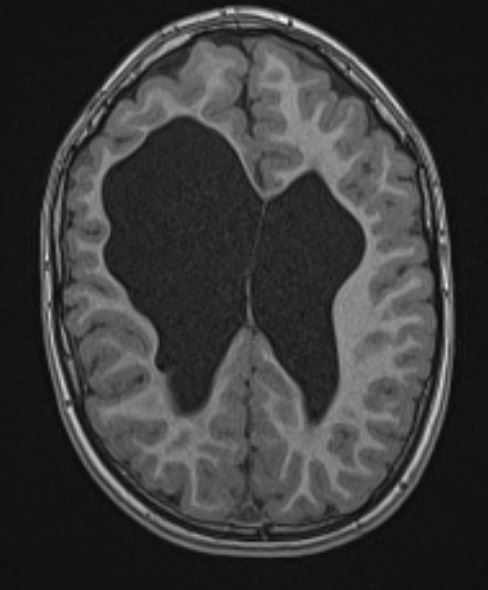

MRI scan:

While there is ventricular enlargement bilaterally, the white matter on the right is disproportionately thin and there is disproportionate right ventricular enlargement. The patient has a congenital left hemiplegia related to periventricular haemorrhage in the perinatal period. EEGs performed in another country demonstrated right frontal inter-ictal epileptiform discharges. Magnetoencephalography demonstrated similar findings.